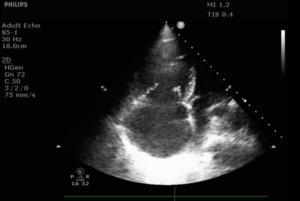

- 3. Ο ρόλος του Υπερήχου Καρδιάς2